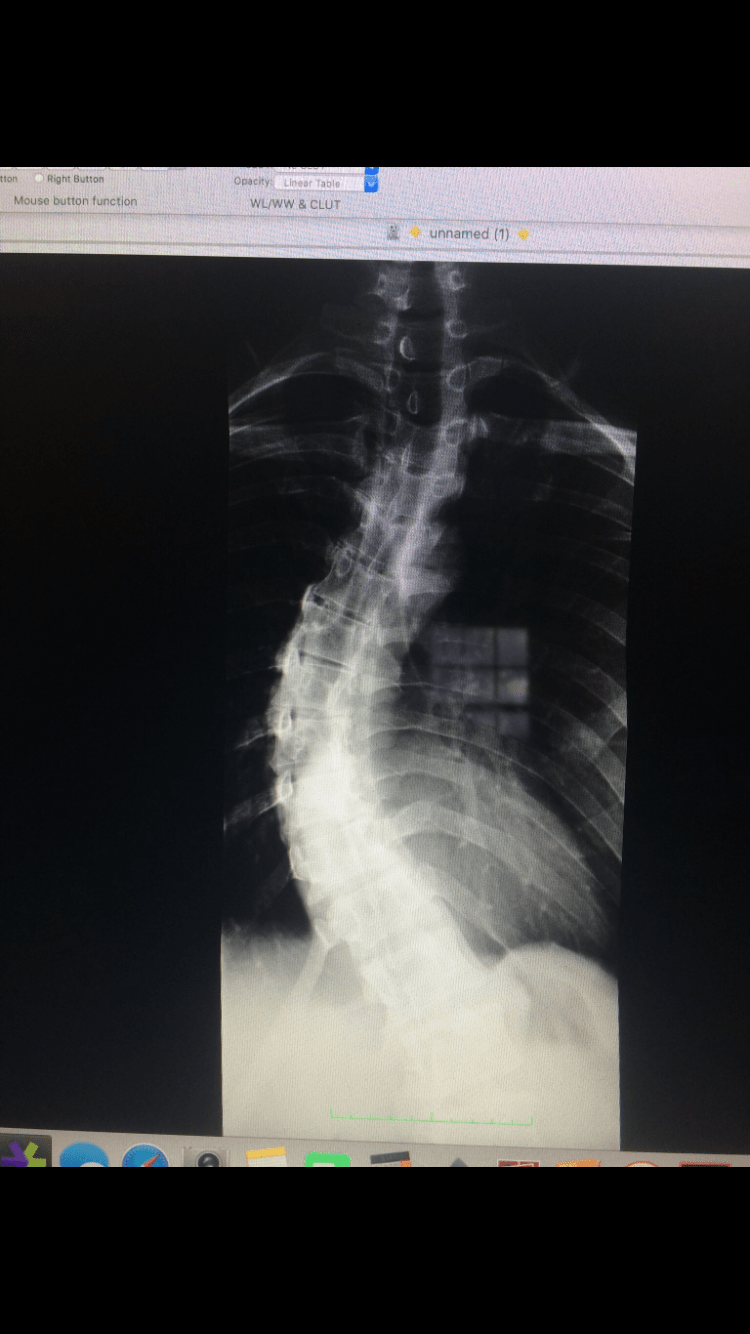

Scoliosis with hyperinflated lungs Xray « PG Blazer Can Scoliosis Affect Your Chest You may feel thoracic scoliosis pain in your back and shoulders. This can result in breathing problems and back pain due to respiratory muscle weakness and chest wall issues. Identifying symptoms of scoliosis is crucial for addressing potential breathing difficulties. However, in cases of cervical scoliosis, moderate scoliosis, or when scoliosis leads to the development of a dowager’s. Severe scoliosis. Can Scoliosis Affect Your Chest.

Chest Xray show fixed scoliotic deformity. The major scoliosis is Can Scoliosis Affect Your Chest You may feel thoracic scoliosis pain in your back and shoulders. Severe scoliosis can restrict spine and chest mobility, affecting lung function. Scoliosis can affect your breathing, but it typically happens in more severe cases, when the curve of your spine puts pressure on your ribcage, making it difficulty for your lungs to. As a result, some people with scoliosis. Can Scoliosis Affect Your Chest.

Chest Xray image shows severe scoliosis. Download Scientific Diagram Can Scoliosis Affect Your Chest Also, a curvature may lead to pain or discomfort in your chest and rib cage because the rib cage is attached to your thoracic. This can result in breathing problems and back pain due to respiratory muscle weakness and chest wall issues. Severe scoliosis can be disabling. Scoliosis can affect your breathing, but it typically happens in more severe cases,. Can Scoliosis Affect Your Chest.